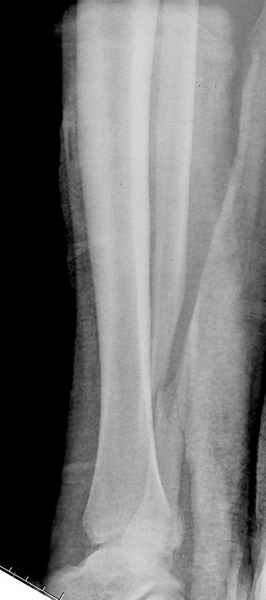

Конечно, компьютерный томограф более информативный метод, но с помощью недорогого обычного стандартного в нейтральном положении стопы: прямого, бокового и косой (ankle mortise) ренгенологического метода можно получить полную информацию о повреждении голеностопного сустава, а сравнительный снимок с другой стороны подтвердить наличие повреждения.

При реконструкции голеностопа, о важности восстановления длины малоберцовой для профилактики пост травматического артроза разбирали в предыдущих дискуссиях. Нарушенную биомеханику голеностопа без восстановления длины малоберцовой, не восстановить только швом медиальной связки.

Расширенная медиальная щель более чем на 4 мм и укорочение малоберцовой более чем 2 мм, а перелом заднего края большеберцовой смещения более 2мм с вовлечением 30% поверхности сустава, считается отходом от нормы голеностопного сустава, и подлежит к оперативному вмещательству.

Здесь похожий случай трехнедельной давности, перелом почти сросся и была укорочена малоберцовая, на операции длину малоберцовой смогли восстановить только после того, когда проксимальнее пластины ввели шуруп и использовали его как толкатель, с помощбю дистракционого инструмента (lamina spreader).